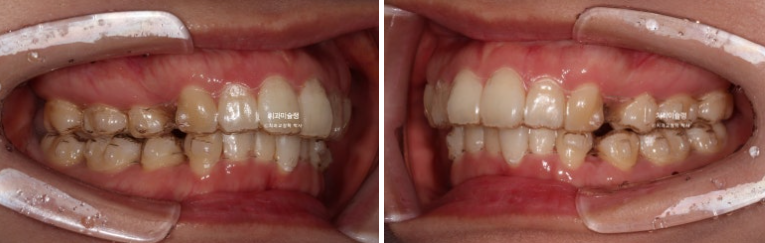

약 한달간의 추가장치 제작기간을 기다려 24년 6월부터 10월까지 23개 추가장치를 모두 낀 후 모습입니다.

24.10

추가장치 치료기간 동안 환자분은 예전처럼 열심히 끼지는 못했고 고무줄도 하루종일 껴주기를 당부드렸지만 개인사정으로 인해 잘때만 착용했습니다.

그래서 6개월이나 추가장치를 꼈지만 과개교합이 그대로 남아있고

발치공간이 놀랍도록 그대로 남아있는 모습입니다.